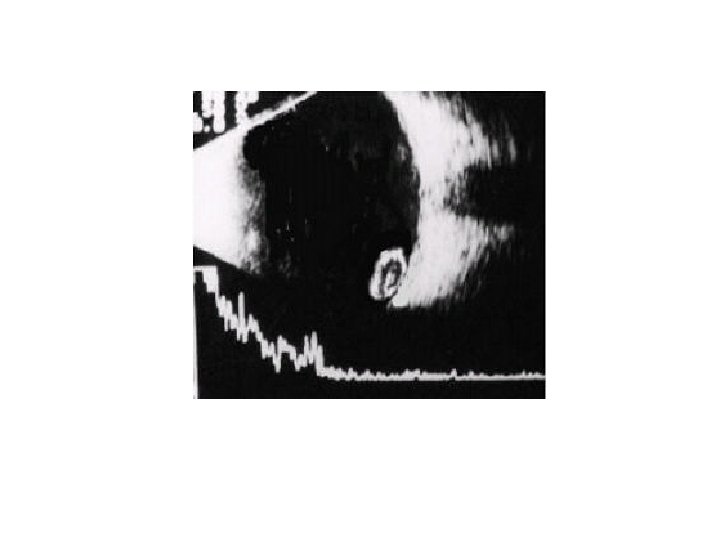

THE ABOVE B-SCAN WAS TAKEN FROM APATIENT WHO HAD A CATARACT SURGERY THE DAY

THE ABOVE B-SCAN WAS TAKEN FROM APATIENT WHO HAD A CATARACT SURGERY THE DAY BEFORE. A. WHAT IS THE DIAGNOSIS? B. SUGGEST TWO PREDISPOSING FACTORS.

• • • a. Expulsive suprachoroidal hemorrhage b. Multiple risk factors: Old age

• • • a. Expulsive suprachoroidal hemorrhage b. Multiple risk factors: Old age Hypertension Atherosclerosis Glaucoma or high preoperative IOP